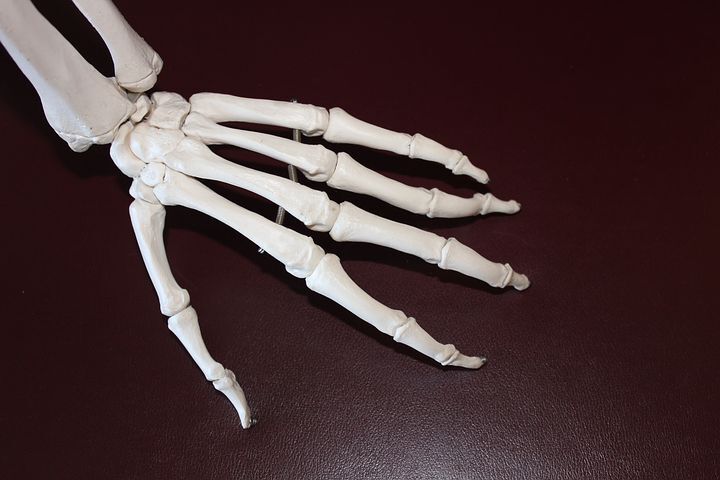

초기증상으로 손이나 발가락의 관절이 대칭으로 부어올라 아침에 굳어지는 경향을보입니다. 발열과 나른함, 식욕 저하 등 전신 증상으로 나타나기도 하는데요.

류마티스 관절염 증상 초기에는 좌우 대칭으로 손가락과 발가락의 관절이 붓고, 아침에 경직을 느끼게 일반적이라 할수 있습니다. 시간이 흐름에따라 관절이 파괴되면, 작은 관절도 생활에 큰 불편함을 초래하게 되는 것입니다.

또한 환자는 무릎 관절이나 엉덩이 등 하체의 큰 관절에까지 영향을 미칠수있고, 걸음이 현저하게 곤란해질 수 있습니다.